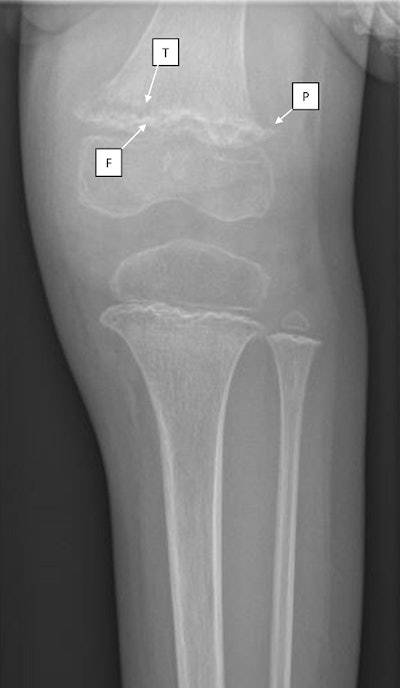

Subsequent images of the girl's distal femur and proximal tibia showed three common radiological findings in scurvy:

- Frankel lines -- dense zones of provisional calcification

- Pelkan spurs -- bony spurring at the periphery of the zone of metaphyseal calcification

- Trümmerfeld zone -- lucent bands in the metaphysis below the Frankel line

Radiograph of the patient's left knee showing dense zones of provisional calcification (F: Fraenkel line) with underlying lucent metaphyseal bands (T: Trummerfeld zone). Also identified is spurring at the distal femur and proximal tibia (P: Pelkan spurs) and a displaced fracture of distal femoral metaphysis. Image courtesy of the Journal of Imaging in Emergency Medicine.The clinical and radiographic characteristics of scurvy are well defined, yet notably, the clinicians identified the disease without a key piece of information -- the girl's vitamin C level.